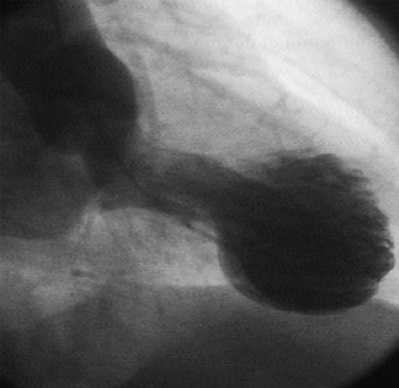

Термин «такоцубо» (tako-tsubo) в переводе с японского языка означает приспособление для ловли осьминогов - керамический горшок с круглым основанием и узким горлышком. Именно такую форму у больных при эхокардиографии приобретает левый желудочек (ЛЖ) в систолу, что объясняется отсутствием сокращения его верхушки с одновременным избыточным сокращением базальных отделов [4].

Наиболее специфичные изменения при ЭХО-кг и контрастной вентрикулографии. Характерен акинез или дискинез верхушки и средней части ЛЖ с гиперконтрактильностью основания и обструкцией выходного тракта ЛЖ. При этом форма ЛЖ напоминает приспособление для ловли осьминогов. Общая систолическая функция снижается, а средняя ФВ ЛЖ варьируется в диапазоне от 20 до 49 процентов [1, 2, 31].

Кардиомиопатия такотсубо была описана впервые в Японии в 1990 г. H. Satoh как преходящие нарушения сократимости миокарда. Классический вариант болезни сопровождается акинезом или дискинезом верхушки сердца с гиперкинезом базальных сегментов. Сердце при этом приобретает своеобразную конфигурацию: левый желудочек в острой фазе по форме напоминает песочные часы или японскую ловушку для осьминогов такотсубо — кувшин с узким горлышком и широким дном. Кадиомиопатия такотсубо - это обратимая дисфункция левого желудочка в ответ на физический или психический стресс, клинически и электрокардиографически напоминающая острый коронарный синдром, преимущественно у женщин в посменопаузе без значимого стеноза коронарных артерий, отличающаяся относительно благоприятным исходом.